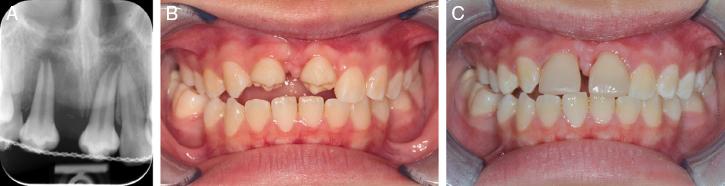

Orthodontic treatment began 6 months after the transplantation. Upper and lower pre-adjusted fixed appliances (MBT prescription, 0.022˝ × 0.028˝ slot; 3MTM Unitek Gemini) were placed. Once in 0.019˝ × 0.025˝ stainless steel wires, space closure was performed to mesialise the transplanted tooth towards the midline. Full-time Class II (3.5 oz, ¼˝) elastics were bilaterally added to support overjet reduction. Nickel-titanium coil springs were placed between #13 and #23 to prepare spaces for composite build-up (Figure 4A-E). The transplanted tooth was reshaped with selective enamel grinding on the palatal cusp to avoid heavy occlusal forces. Finishing step bends were placed to idealise the gingival margins of the transplanted teeth and increase palatal root torque on the upper incisors. The total orthodontic treatment time was 29 months. Following removal of the orthodontic appliances, the prosthodontist was able to carry out composite resin build-ups on #13 – #23. The patient was fitted with an upper fixed bonded retainer and asked to wear upper and lower vacuum-formed retainers on a night-time basis (Figure 5A-G).

(A–E) Midtreatment intra-oral photographs.